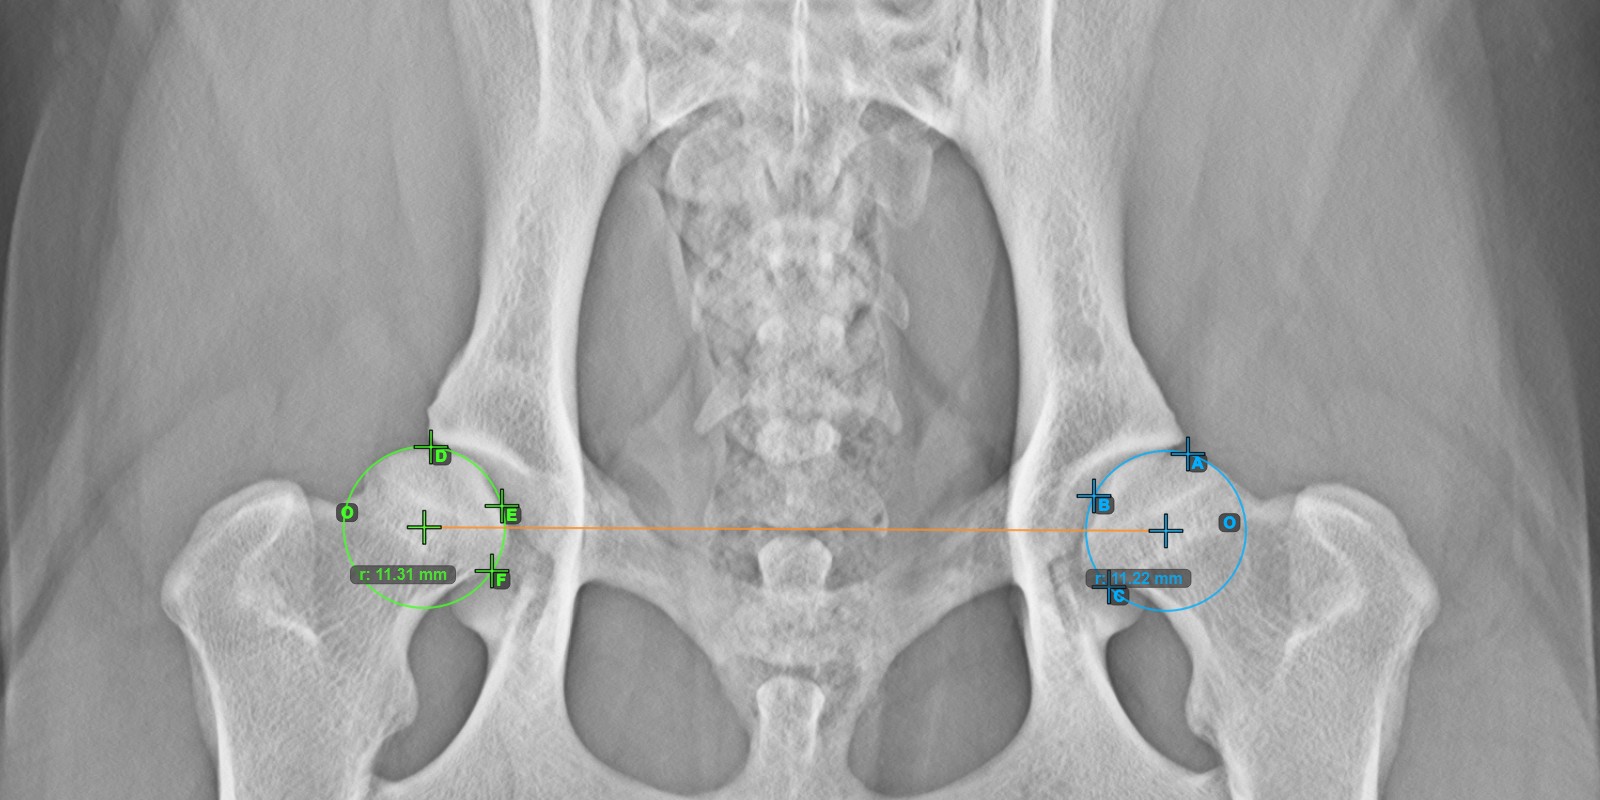

Mark the three points on the articular surface of the left Caput Femoris (outside of the Fovea Capitilis). Regardless of the order, make sure to mark the most cranial point, the most caudal point and the midpoint of the femoral head. A circle will be automatically constructed based on the three placed points.

The image below depicts the typical placement of the three points on the articular surface of the left Caput Femoris.